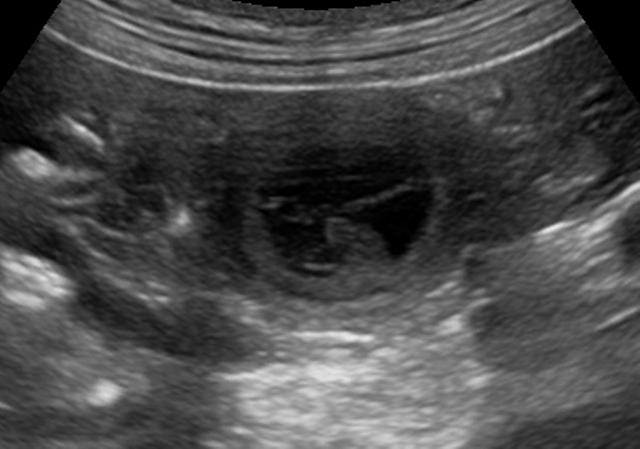

Auf dem Ultraschallbild unten sieht man deutlich, wie klein die Mäuschen noch sind.

Von einem Querstrich zum nächsten ist es ein Zentimeter...

Sie liegen zwar in der gebogenen Embryonalstellung und man sieht ja im Ultraschall

quasi nur eine "Scheibe" aber sie sind wirklich noch winzig :) :)

Hoffen wir, dass sie sich - in Joes Bauch geborgen - zu gesunden kleinen Wonneproppen entwickeln!!!